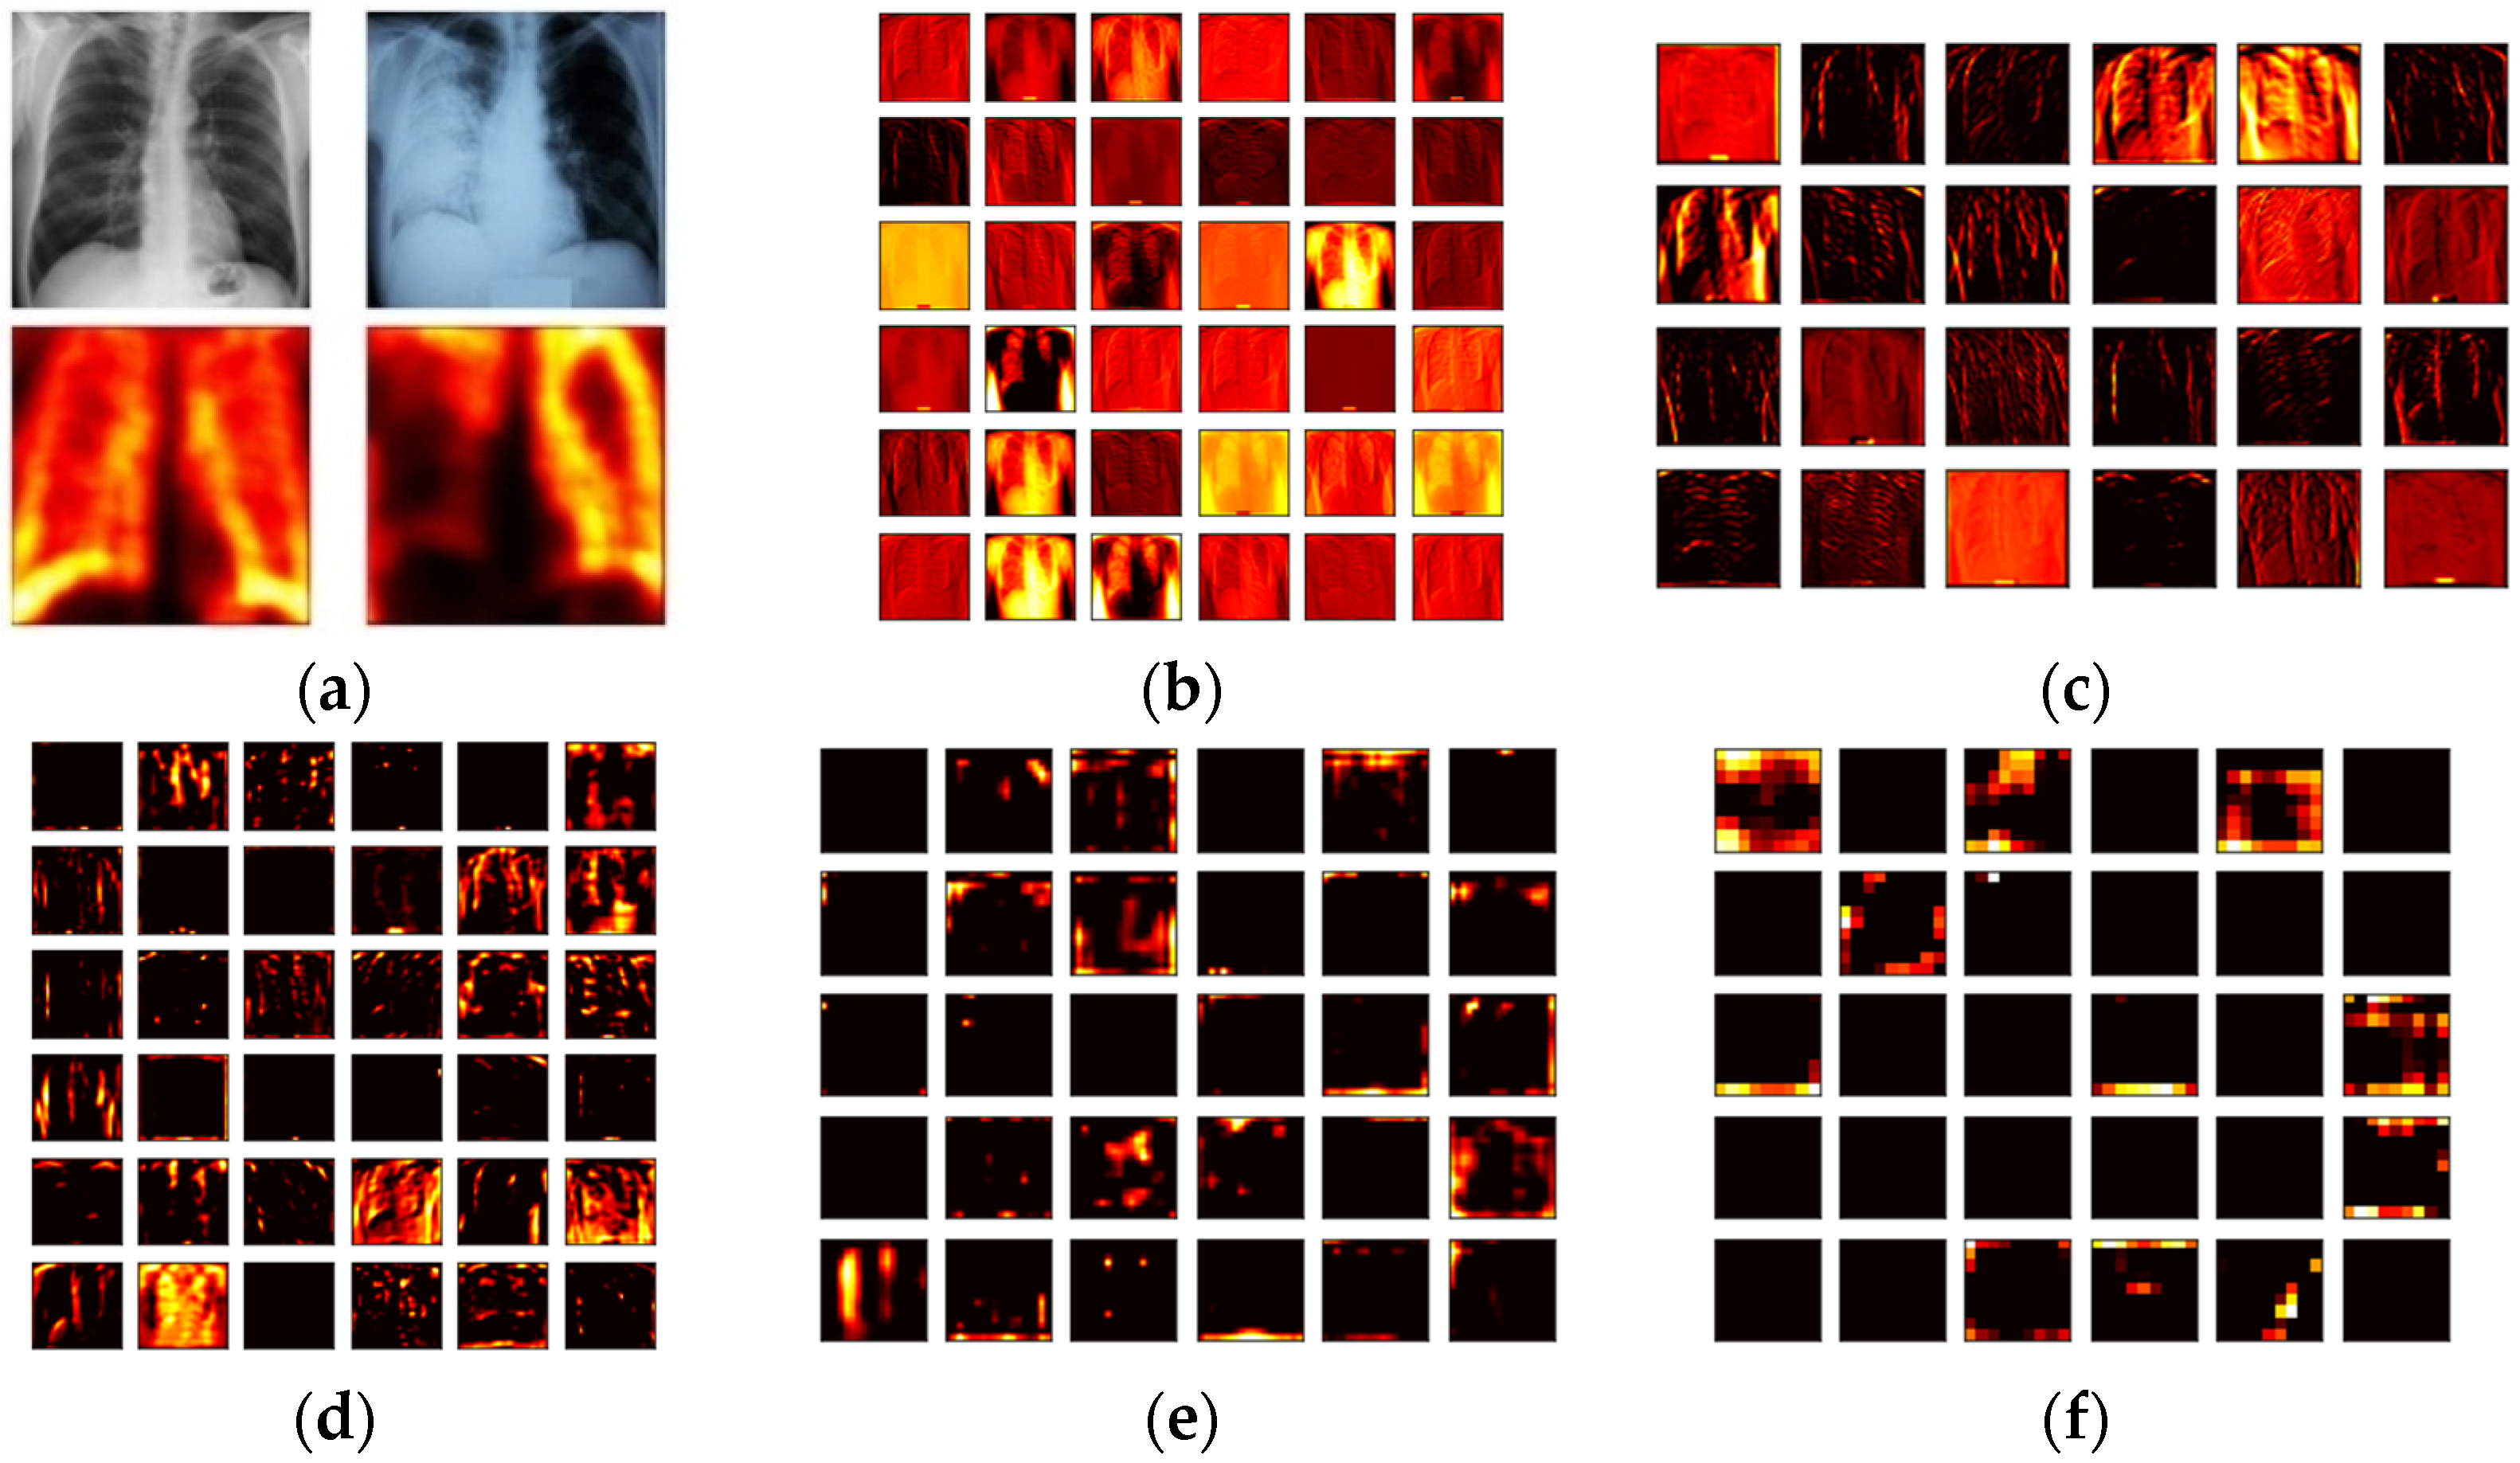

3.2. Pre-Trained VGG19

3.3. Feature Extraction

3.3.1. Deep-Learning-Features

3.3.2. Machine-Learning-Features